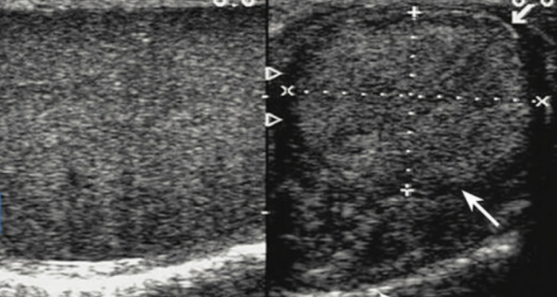

4.睾丸萎缩

睾丸大小因人而异,正常大小在15-20ml之间。萎缩的睾丸体积明显缩小,质地软。通常合并睾丸生精功能衰竭的表现,睾丸活检仍然是诊断睾丸功能衰竭的金标准。

超声表现:萎缩睾丸体积小、回声减低;血流信号减少或消失。